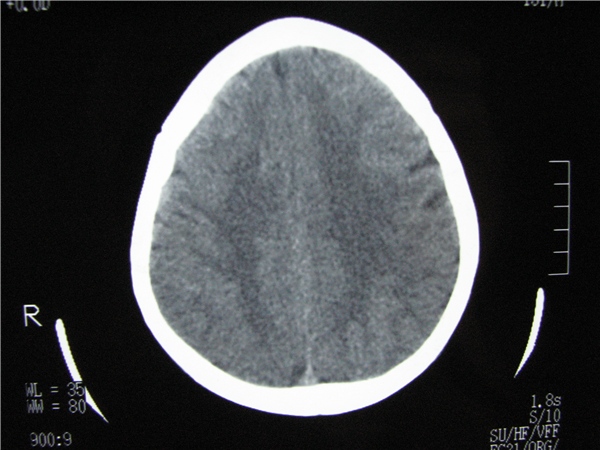

m 15y 头痛,以前有外伤史请老师看看除了囊肿还有别的吗?

蛛网膜囊肿。眼拙,看不出别的,倒是看到了双侧大脑中动脉影,类似“致密动脉征”。

双侧侧裂池和纵裂池近前颅窝蛛网膜囊肿。

无明显占位及负占位效应,考虑软化灶并脑室穿通畸形囊肿、局限性脑萎缩

蛛网膜囊肿,不能除外脑穿通畸形,支持。